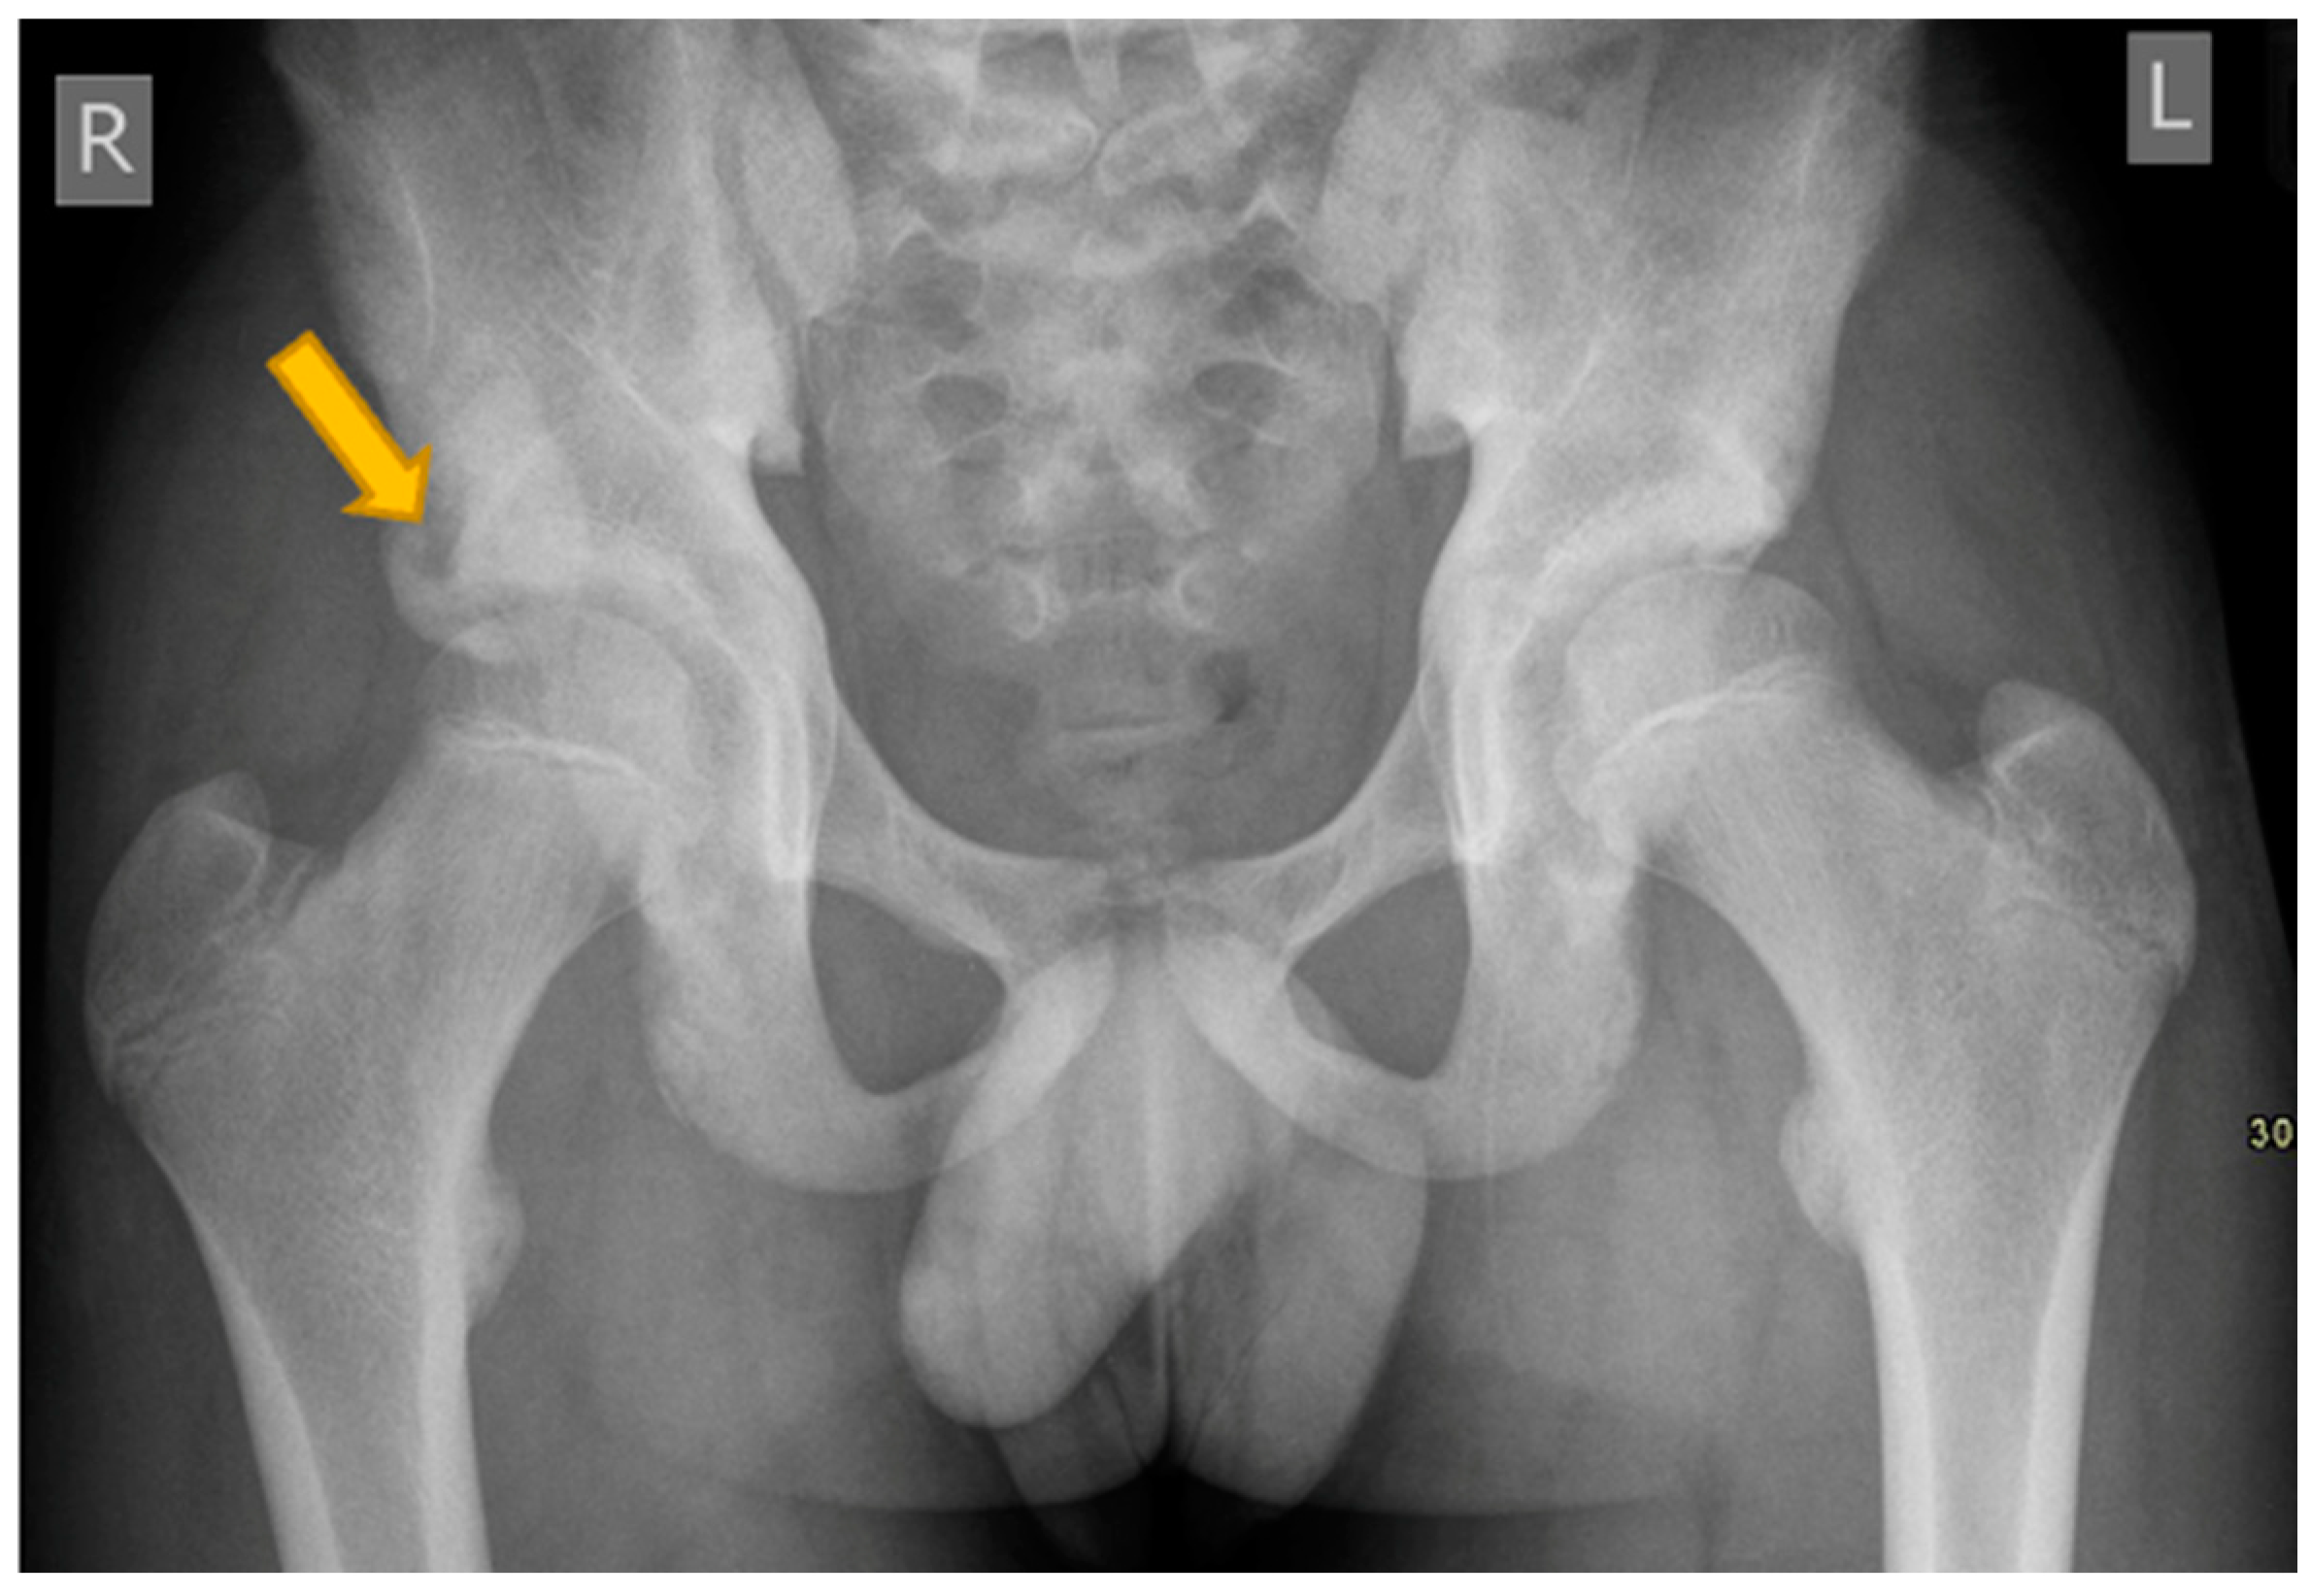

12. Simple Bone Cyst of Neck of Femur